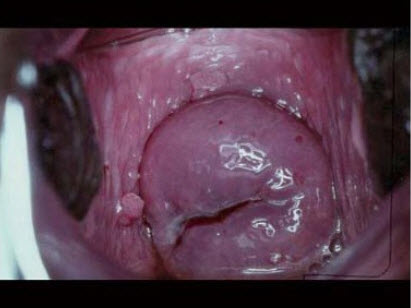

女性,22岁,服条员,多个性伴侣。妇科检查:如图。最可能的诊断为()

A . 阴道尖锐湿疣

B . 细菌性阴道病

C . 滴虫阴道炎

D . 细菌性阴道炎

E . 生殖器疱疹

[单选题]女性,22岁,服务员,多个性伴侣。妇科检查:如图。最可能的诊断为()A .阴道尖锐湿疣B .细菌性阴道病C .滴虫阴道炎D .细菌性阴道炎E .生殖器疱疹